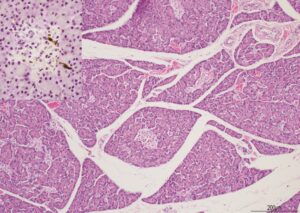

Insulin expression in β cells is reduced within islets before islet loss in diabetic cats by Valeria Bergomi and colleagues at the University of Cambridge

Dr Kate Hughes received BSAVA PetSavers funding for a master’s degree by research to explore pancreatic islets in canine and feline diabetes. Her student, Valeria Bergomi, found a significantly reduced overall islet mass in diabetic cats (standard error=0.0389, t value=−4.490, P=0.0003) and significantly lower insulin expression from β cells prior to cell loss compared with control cats, suggesting reduced insulin expression occurs before islet loss in diabetic cats. The paper reporting this is published in the November 2022 issue of JSAP, and also shows the value of using the CUBIC method to render tissue transparent and investigate the 3D islet microanatomy of cats.

Read more and access the publication here